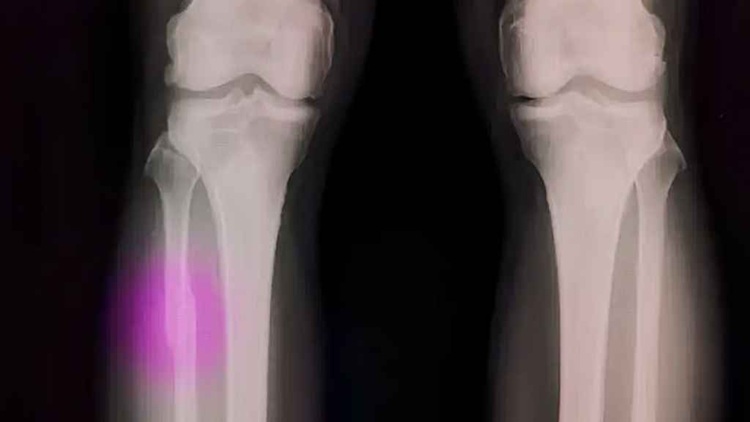

‘বায়োপেন’ প্রযুক্তি অর্থোপেডিক চিকিৎসায় এক যুগান্তকারী পরিবর্তন আনতে যাচ্ছে

বর্তমানে হাড় ভাঙার চিকিৎসায় প্লাস্টার, ধাতব পাত বা স্ক্রু ব্যবহার করা হলেও নতুন এই ‘বায়োপেন’ প্রযুক্তি অর্থোপেডিক চিকিৎসায় এক যুগান্তকারী পরিবর্তন আনতে যাচ্ছে। চিকিৎসকেরা সরাসরি অপারেশনের সময় ক্ষতিগ্রস্ত হাড়ের ওপর এই আঠা প্রয়োগ করে অত্যন্ত নিখুঁতভাবে হাড় স্থির করতে পারবেন।